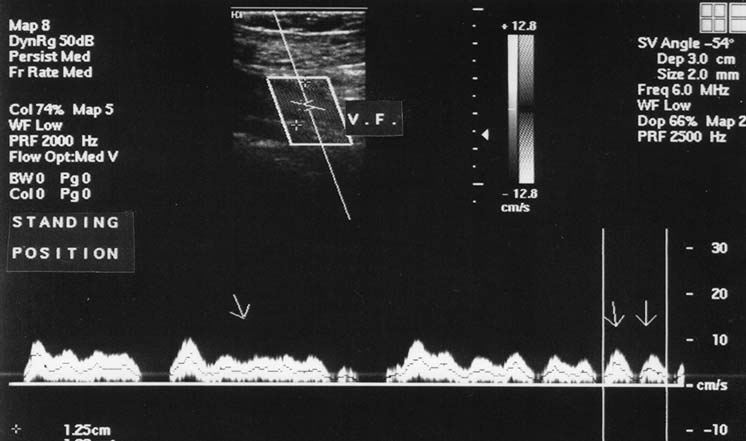

Скорость венозного кровотока увеличивается от периферических вен к центральным. При переходе в вертикальное положение она уменьшается (в среднем на 75%), дыхательные волны при этом становятся более выраженными. При глубоком вдохе и задержке дыхания на вдохе скорость венозного кровотока уменьшается. По этой причине для корректной оценки венозного возврата пациента просят задержать дыхание на выдохе. При этом допплеровский спектр венозного кровотока становится низкоамплитудным непрерывноволновым с небольшими волнами, соответствующими частоте ритма сердца (рис. 3).

Рис. 3. Кровоток в бедренной вене в спектральном допплеровском режиме в положении стоя (двумя стрелками указаны волны при задержке дыхания)

Такой характер кровотока свидетельствует о том, что в вертикальном положении влияние фактора «vis a tergo» на венозный возврат снижается, и основным становится фактор «vis a fronte».